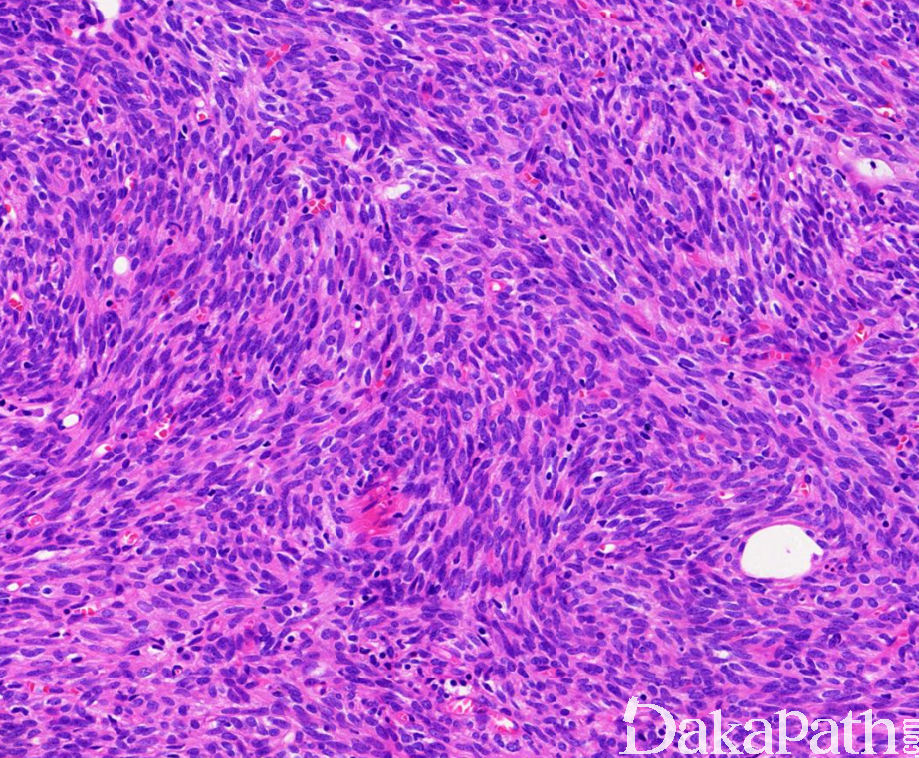

- 低倍镜下肿瘤具有完整或不完整的纤维性包膜,可由粗的纤维带分隔成小叶,部分病例可见微囊,多位于被膜下区域;

- 肿瘤细胞可形成多种形态结构。包括菊型团(可伴或不伴中心腔隙)、腺管状、肾小球样、囊内 Masson 血管瘤样乳头状突起,也可呈旋涡状、束状、席纹状等排列。同一肿瘤可见多种形态混合。

- 常见血管外皮瘤样结构,血管周围裂隙比其它类型胸腺瘤少见;

- 肿瘤细胞形态温和,梭形或卵圆形,核圆形或卵圆形,染色质细粉尘状,核仁不明显;

- 有些病例部分细胞呈多角形,但核仍为一致的圆形,染色质与梭形细胞相似,呈细粉尘状,核仁不明显;

- 核分裂像少见,通常<4/2mm2,;